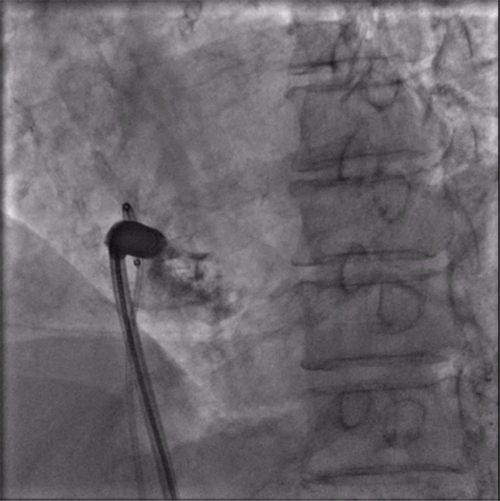

LAO造影确认指向间隔部